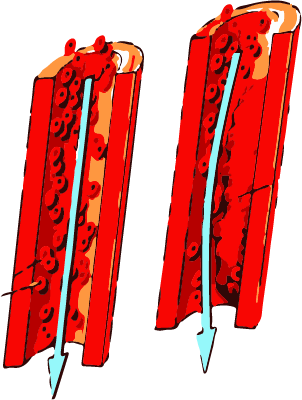

Silpnas arba netvarkingai srautas kraujo paprastai įvyksta giliųjų venų trombozė, kurią sudaro fibrino ir raudonųjų kraujo kūnelių santykinai mažai trombocitų. Trombozė sukelia aktyvuotų koaguliacijos faktorių vietoje kaupiasi dėl sumažėjusio poveikio gamtinių antikoagulianto kraujyje. Venų trombozė paprastai prasideda, kur yra ryškiausi vėlavimas vožtuvų kišenių ir kraujagyslių sužalojimo vietoje ir taip pat gali būti priežastis žalą kateterį, kraujo stasis endotelio po operacijos, ilgu sėdėjimu su kojų nuleisti (sunkvežimių vairuotojai, lėktuvas skrydžio) , geriamųjų kontraceptikų vartojimą. Didėjimas vožtuvų sinusų gelmių trombocitų paprastai yra labiausiai venų trombozės pradžia. Giliųjų venų trombozė, venų sinusų veršelio raumenų dažniausiai atsitinka. Giliųjų venų trombozė, taip pat gali atsirasti kitų blauzdos, šlaunies venų varikoze. Kairės kojos yra labiau pažeidžiami atsiranda trombozės ir be gydymo proksimalinės giliųjų venų trombozės 15-20% pacientams, sergantiems kenčia nuo plaučių emboliją,. Jei krešulys, kuris yra sukurtas Kraujo koaguliantai kaupimo, didėja tokiu mastu, gauti paleistas iš venų sienelių, jis sukuria keliaujantiems trombas, žinomas kaip embolija, kuri gali sukelti širdies priepuolį ar insultą. Jis taip pat naudojamas kaip terminas, tromboflebitas, nes trombozė visada lydi uždegimas venose ar flebitas.